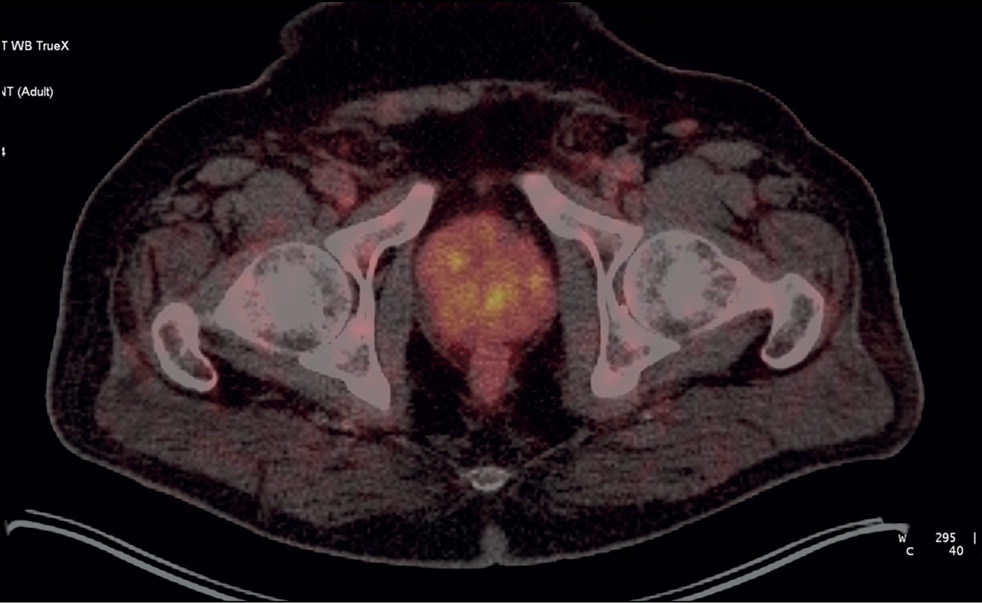

Case report 6

Patient M., 65 years old, was diagnosed with benign prostatic hyperplasia. Due to an increased PSA level of 4.5 ng/mL, a US-guided multifocal biopsy was performed with no histological evidence of cancer. A repeat biopsy was performed 3 months later and revealed no malignant tumor. SPECT/CT with 99mTc-HYNIC-PSMA revealed a site of RP accumulation in the prostate tissue (Figure 7). A CT-guided targeted biopsy was performed, and the following diagnosis was morphologically confirmed: adenocarcinoma, Gleason 7 (4 + 3). When planning low-dose brachytherapy using 125I microsources, SPECT/CT data were entered into the dosimetry planning system. On October 4, 2020, the focal implantation of 125I microsources was performed under a CT guide using pararectal access based on data on local isotope accumulation in the prostate tissue. The follow-up examination (January 2023) showed a 0.11-ng/mL PSA level.

Fig. 7. Patient M., 65 years old, SPECT/CT with 99mTc-HYNIC-PSMA: Site of radiopharmaceutical accumulation in the transition zone (at the border of the middle third and the base) of the left prostate lobe.